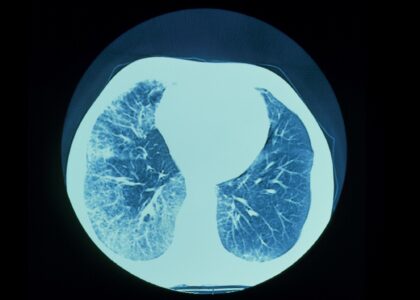

Global Progressive Fibrosing Interstitial Lung Diseases (PFILD) Treatment